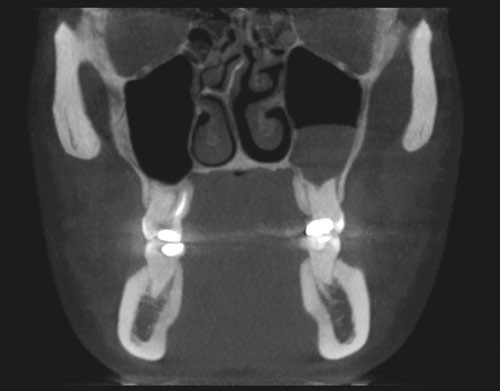

Figs 3 and 4 show CBCT images of anatomical structures in the nose, maxilla, larynx and throat. The two-dimensional image shows retention polyps in the left maxillary sinus (fig. 3), but no pathological airway changes were found in the larynx or throat (fig. 4).

Figure 3  Coronal CBCT sections of the skull with fluid in the sinus maxillaris